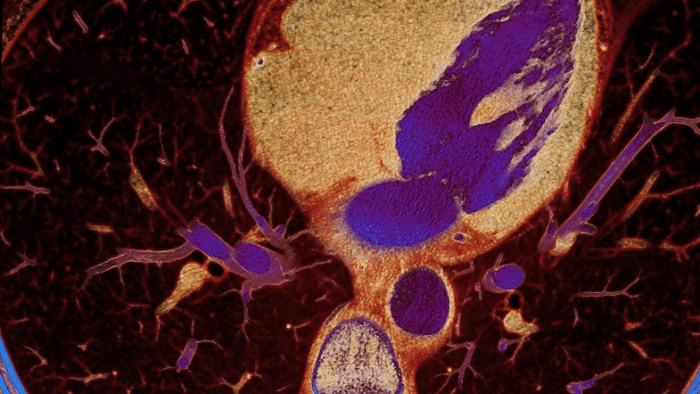

Unlike traditional CT images, spectral-detector CT images capture spectral information 100% of the time —without special planning or set-up. That means you can analyze the spectral data in any image retrospectively, using a variety of spectral viewing tools. You can, for example, adjust the monoenergetic level or get Zeffective maps.

Can you see the difference?

Move the slider to reveal spectral results when compared to conventional CT.

Conventional CT Spectral result

Spectral detector simultaneously absorbs and differentiates high and low energy from a single polyenergetic X-ray beam. Spectral results are acquired within a single scan without the need for special modes.

Detector-based spectral CT simultaneously absorbs high and low energies in the same time and space.